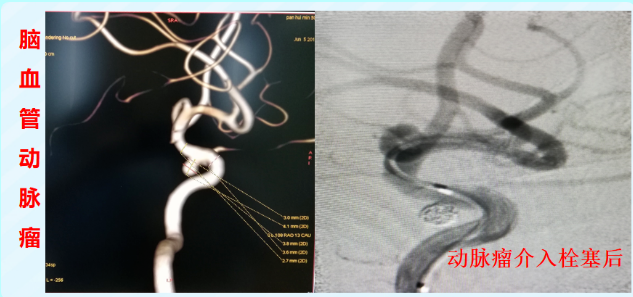

脑动脉瘤:在动脉瘤腔内填入柔软的弹簧圈,或放置密网支架,从内部加固血管壁,预防其破裂出血这一致命风险。